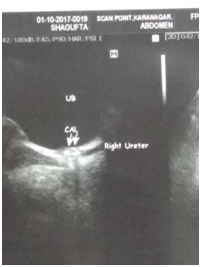

All patients who reported within 1-2 days of ureteric colic were examined, and subjected to Haemogram, KFT, Urine examination, Ultrasound and NCCT Scan (Figure 1&2) to document ureteric calculi at the time of colic with respect to location, side and size of the stone. Age and sex of the patient was noted down and SOADS regime was started for a period of 4 weeks maximum after which this MET was stopped. The routine follow up examination were performed, using the same tools to evaluate the success of the treatment after every week till 4 weeks of study period. Patients were instructed to discontinue the study medication after spontaneous stone expulsion and date of expulsion is to be recorded. For patients without stone in urinary tract on final USG/NCCT but unnoticed stone expulsion, the date of last positive stone status is to be recorded (Figure 3). For the children the dosage of the SOADS regime was half the dosage. Two - three litres of fluid which consists of Lemon juices, Oranges juices and clear water or Tea. This regime was continued for 2 weeks after which again assessment was made and if the stone did not pass then it was continued for another 2 weeks. Treatment was considered successful when stone was expelled within 4 weeks. After 4 weeks, patients who did not pass the stone were advised to undergo minimally invasive surgery depending upon the stone size and location.

Figure 2 Ultrasound showing upper ureteric calculi and uvj calculi.